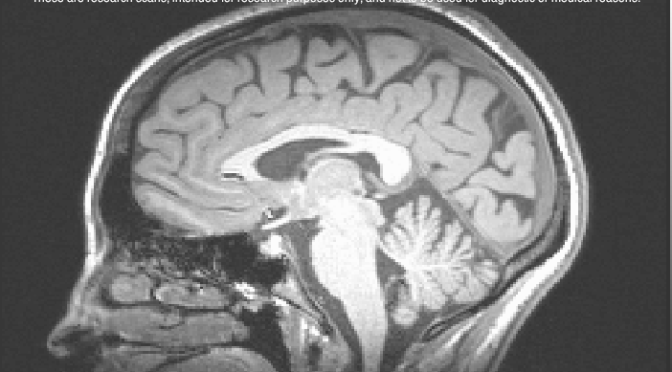

Two days ago they did a test on my memory and how the brain stores information. They sat me at a computer and they would flash a word at me like ‘giraffe’. I would then as quickly as possible determine whether it is living or non living using the buttons strapped to my fingers. From there I had to do this really quick mathematical addition in my head with numbers flashing up on the screen at me and then decide whether the number they showed me at the end was the correct answer to the addition. From there, you then have to recall the word. They do all of this while you are strapped into an MRI machine measuring the different activities of your brain in doing the sums and the recall. The hypothesis that they are testing is whether or not the long term memory is more effective when you focus more on the word that you have to remember or when you are busy with a distractor task, ie. the maths sums. Strangely enough, they have been finding that the words that you do the distractor task with are more likely to be remembered long term as the way that these words are processed in the brain is different. Really interesting study. Probably why I did so well at university studying with the TV on, the radio on, talking on the phone and trying to read at the same time! Me being as competitive as I am too, I had to try and beat my own scores and the scores of others with the decision making and the maths. I was killing it to a point. 85-90% 🙂 Not bad when the average is around 60-70% for the maths! Looks like all of the learning books and the brain training games are paying off!

Of the most lucrative and probably most uncomfortable of the medical tests that I have done was the PET scan. After doing a two hour screening of different IQ type tests with shapes and logic and a psychological evaluation, they sent me off to do the scan. They put me in a hospital gown, laid me onto the table and then started to put in the arterial line in my left wrist. Luckily they hit it the first time so it wasn’t too bad in the healing process. They put the radiotracer into my right arm and then I pretty much laid in the machine for 2 hours while they scanned my brain to see where the radiotracer was collecting and if it was more concentrated in specific areas of the brain or not for a specific enzyme that they are attributing to swelling in the brain that is related to depression.

They took different blood samples from my wrist throughout the experiment to look at the concentration of the radiotracer in my blood and I have to say it wasn’t the most comfortable of situations. What I didn’t realize was that they actually put a plaster cast thing over your face to lock it into place for the scan so that your head doesn’t move. So here I am, head locked in in a plaster cast, needles sticking out of my arms, the most ADHD I have ever been and all I wanted to do was go for a dance or move around or do something! The two hours were finally up, I had my arterial line out, went for a 20 minute MRI and took my cash for the day. More money than I would have earned in the space of a week and a half working for minimum wage in Toronto on half a day of being a guinea pig for the advancement of science. I will most certainly take that.